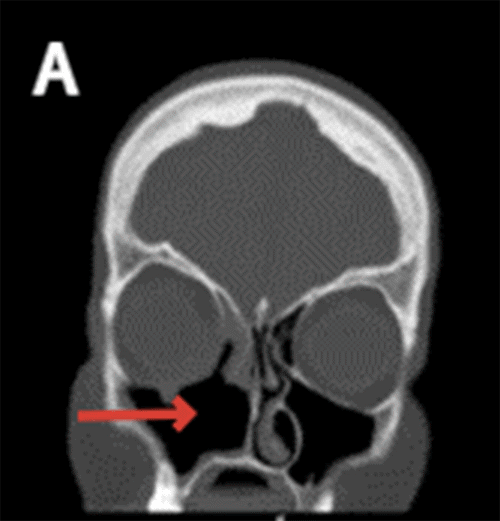

Non-contrast head CT reported the absence of the medial wall of the right maxillary sinus as well as the right inferior nasal turbinate with moderate mucosal thickening within the right frontal, bilateral ethmoid, right sphenoid, and maxillary sinuses indicating chronic sinusitis (Figure 1).

Figure 1. CT Imaging Demonstrating Patient's Extensive Bony Destruction. Published with Permission

B) Arrow pointing at loss of right lamina papracea

Patients with chronic invasive sinusitis with mucormycosis present with non-specific symptoms, including facial pain, facial pressure, headache, mucoid nasal discharge, fevers, nasal congestion, periorbital edema, proptosis, blindness, and cacosmia with the most frequently reported of these being unilateral facial pain.1 Of note, our patient reported several symptoms, including nasal congestion, facial pressure, visual changes, eye drooping, and sinus drainage, for months before presenting to our office. Diagnostic workup includes head CT, MRI, nasal endoscopy, and surgical intervention to retrieve cultures and tissue biopsies for pathologic confirmation. Imaging modalities can reveal the destruction of nasal turbinates, bony erosions, and hyperattenuating allergic mucin. Our patient's diagnostic imaging revealed extensive underlying bony destruction despite having minimal dysmorphic facial features before surgical intervention.